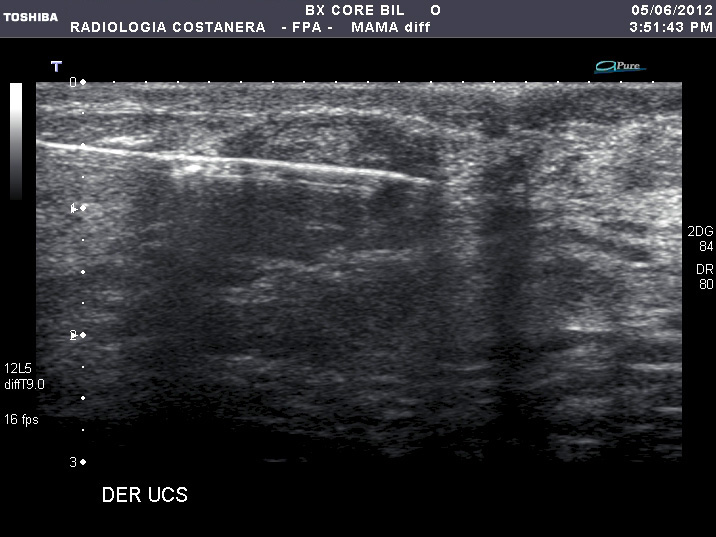

También es posible, guiado por ultrasonido, realizar biopsias de distintas partes del cuerpo, siendo más corrientes en  mamas, tiroides y próstata.